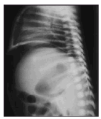

Se trata de un recién nacido a término mujer, primera hija de padres jóvenes y sanos, procedente de embarazo controlado. La madre recibió tratamiento con diazepam oral por ansiedad los 4 días previos al parto. Parto vaginal y eutócico a las 38 semanas de edad gestacional. Test de Apgar de 9 al minuto y 10 a los 5 minutos. Peso al nacimiento: 2.730 g. Las primeras 48 h de vida permanece en la maternidad, asintomática, recibiendo lactancia materna exclusiva, con tolerancia adecuada, realizando varias deposiciones meconiales. El tercer día aparece rechazo de tomas, afectación del estado general, color grisáceo de piel y ligera distensión abdominal. Se solicita analítica sanguínea, obteniendo valores hematocitométricos y bioquímica normal salvo PCR de 68 mg/l. Es ingresada en la unidad de neonatología donde se instaura perfusión hidroelectrolítica, así como antibioticoterapia intravenosa con ampicilina y gentamicina. La gasometría al ingreso muestra una leve acidosis metabólica. En la radiología practicada se aprecia en la proyección anteroposterior (fig. 1) el signo del balón de rugby, así como elevación de ambos hemidiafragmas. En la radiografía lateral (fig. 2) el aire libre perfila el límite del hígado y del diafragma. Otros signos de neumoperitoneo están presentes como es la visualización de la pared de asas intestinales. En las 2 h siguientes la niña presenta deterioro progresivo con incremento de la distensión abdominal, taquicardia y taquipnea que mejoran tras la colocación de sondas nasogástrica y rectal. Se comprueba elevación de la PCR hasta 203 mg/l sin alteraciones significativas en la hematocitometría. Presenta una calcemia de 6,6 mg/dl. El hemocultivo fue negativo. Se hace el diagnóstico de perforación intestinal, añadiendo clindamicina al tratamiento y se traslada al Servicio de Cirugía Pediátrica del Hospital General Yagüe de Burgos, donde se practica laparotomía. Los hallazgos operatorios muestran una peritonitis biliar por perforación en la primera porción del duodeno, lineal y de bordes netos, de la totalidad de la cara anterior. Se procede al cierre en 2 planos. Se establece sondaje gastroyeyunal a través de gastrotomía de Stamm y drenajes de Penrose a nivel parietocólico bilateral que se retiran en el quinto día de postoperatorio. A los 12 días se retira la sonda de gastrostomía, siendo dada de alta a la edad de 16 días, asintomática, con excelente tolerancia digestiva. En las revisiones posteriores se constata la absoluta normalidad clínica y nutricional de la paciente.

Figura 2. Aire libre interpuesto entre el diafragma y el borde hepático anterosuperior.